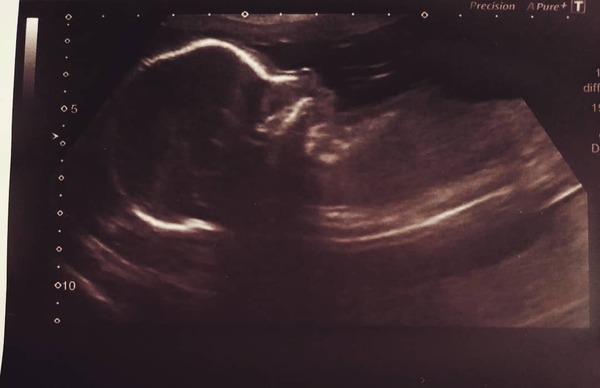

So glad to see everyone’s scans going well. I also had mine and everything looked perfect, couldn’t believe how clear the picture was. Midwife said I have strong ab muscles so she’s sitting down by my pelvis still 💕